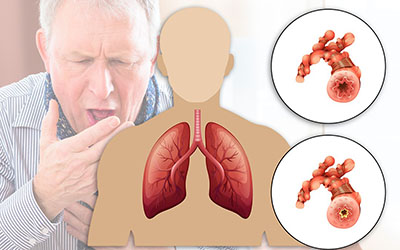

شُشها، جگر سفید یا همان ریه قسمت اصلی دستگاه تنفسی انسان است، این ارگان حیاتی، به شکل نیمه مخروطی هستند و با حالتی اسفنج گونه اطراف حفره سینه را میپوشانند. در ششها گلبول قرمز خون اکسیژن را به دیگر سلولهای بدن میرسانند. همچنین دی اکسید کربن را از جریان خون جدا میکند و در یک تبادل گازی دم و بازدم اکسیژن را از هوا گرفته و دی اکسید کربن را طی بازدم به هوا منتقل میکند.

ما انسانها دو عدد شُش در قفسه سینهمان داریم که یکی کوچک و دیگری کمی بزرگتر است. در یک مسیر هوایی در داخل بدن که از قسمت نای آغاز میشود و به شاخههای نایژه و نایژک میرسد هوا و اکسیژن موجود در آن از طریق همین مسیر هوایی وارد ریهها شده و عمل تنفس انجام میگیرد. بافت ریهها به گونهای است که میتواند در اثر بیماریهای مختلف تنفسی دچار آسیبدیدگی گردد.

بیماریهای مرتبط با ریهها و دستگاه تنفسی

از جمله بیماریهای ریوی و تنفسی رایج بین افراد میتوان به سینهپهلو، آسم و سرطان ریه اشاره کرد، همچنین بیماریهای مزمن انسدادی ریه مثل برونشیت نیز شایع است که تحت تاثیر عواملی مانند مصرف سیگار یا استشمام مواد سمی، گرد و غبار و دود انواع سوختهای زغالی و... ایجاد یا تشدید میشوند.